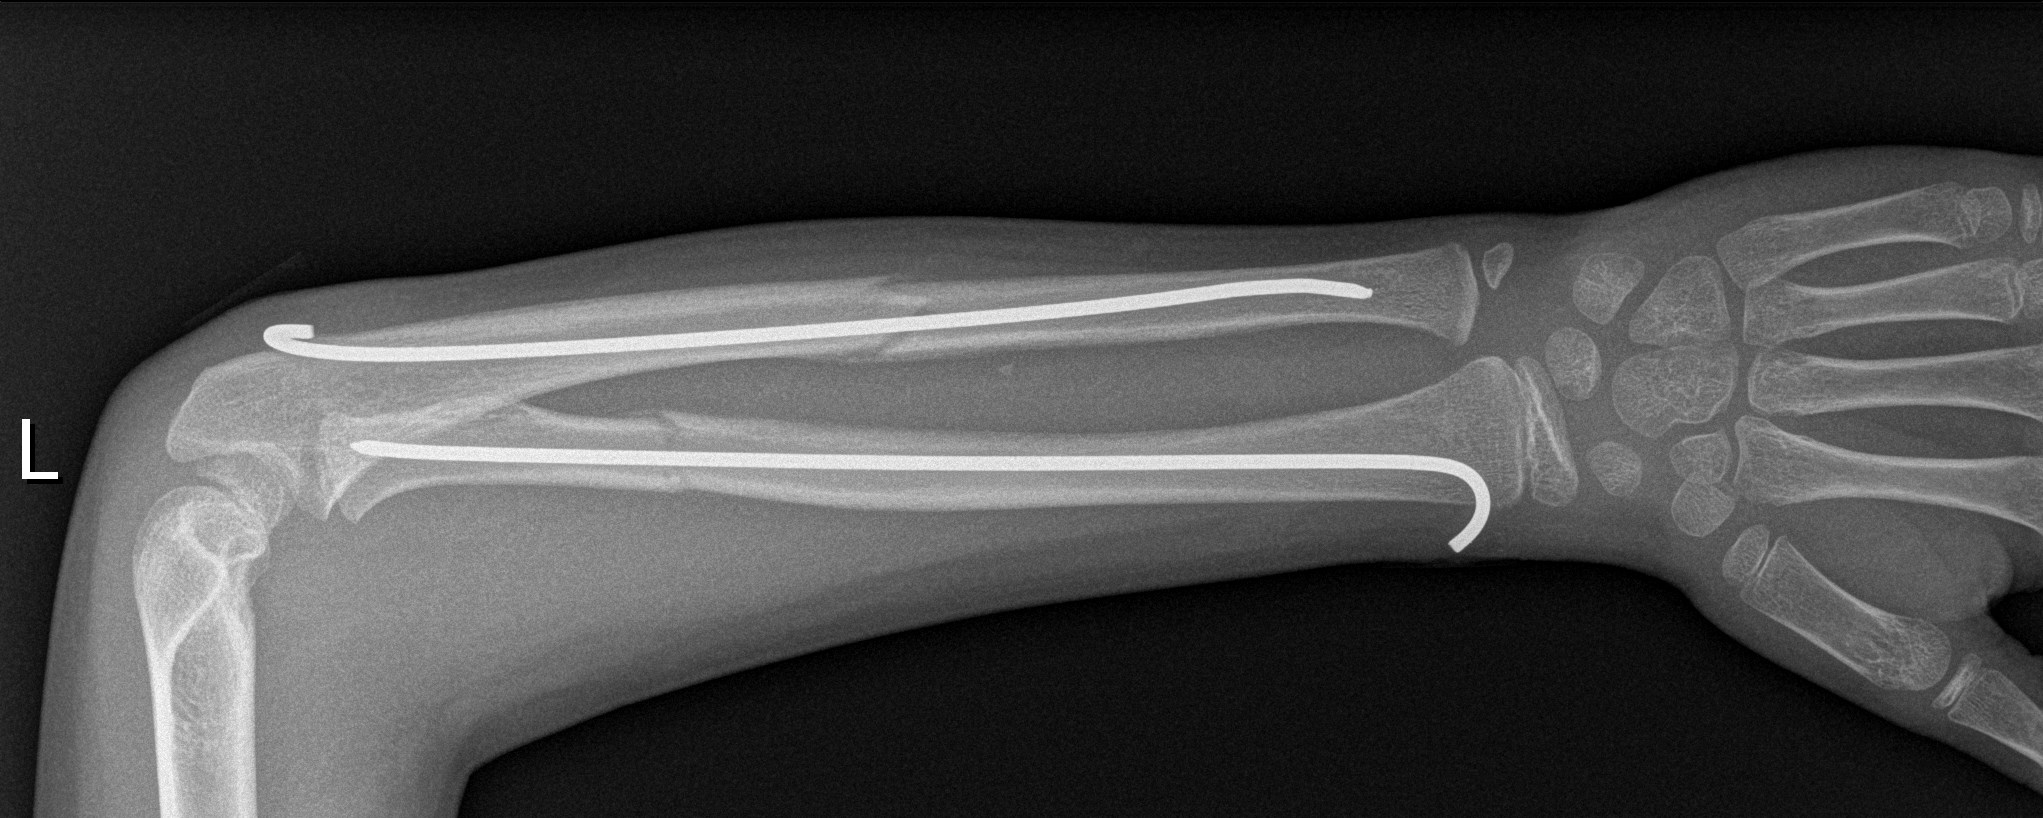

Der Oberarm [humerus] besteht aus dem Oberarmknochen – welcher der längste Knochen der oberen Extremitiät ist – und Muskulatur. Speiche und Elle sind bilden den Unterarm [antebrachium], umgeben von Streck- und Beugesehnen.

▶︎ Fraktur von Elle und | oder Speiche